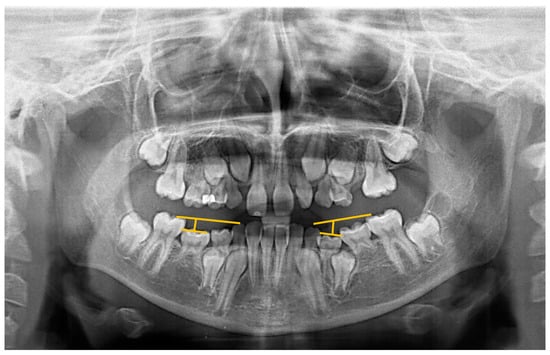

- Odeh, R.; Mihailidis, S.; Townsend, G.; Lähdesmäki, R.; Hughes, T.; Brook, A. Prevalence of infraocclusion of primary molars determined using a new 2D image analysis methodology. Aust. Dent. J. 2016, 61, 183–189. [Google Scholar] [CrossRef] [PubMed]

| IODM * | MIH | No MIH | p |

|---|---|---|---|

| Yes | 55 (27%) | 39 (19.2%) | 0.082 |

| No | 149 (73%) | 164 (80.8%) | |

| Total | 204 | 203 |